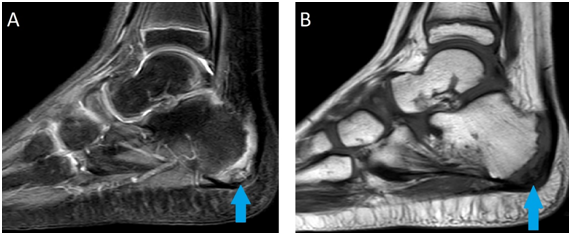

8 years-old boy with pain in the heel of both feet for three months. The pain started when they started to play basketball. Deny traumas and surgeries. Indicates pain at local palpation and walking. MRI demonstrated irregularity of calcaneal apophysis with important edema, corresponding to Sever's disease, with discrete edema of surrounding subcutaneous tissue, in both feet (Figure 1) (Figure 2).

Figure 1 Sagittal MRI of the right foot in T2 SPIR sequence in A and T1 sequence in B demonstrating irregularity of calcaneal apophysis with important edema, corresponding to Sever's disease (blue arrow).